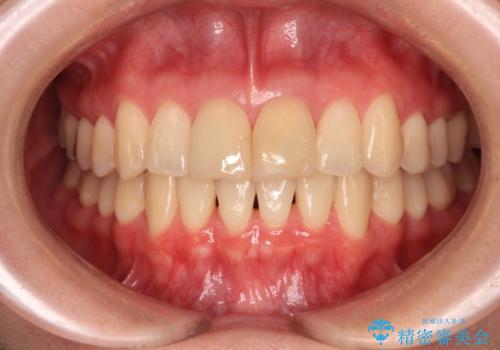

変色した前歯 オールセラミッククラウンにより審美歯科治療

- 神経を取り除いたことで経年変色した前歯2本を気にして来院された患者様です。

根管治療を行う必要はないと判断し、双方の歯にグラスファイバーを含有した土台を植立してオールセラミッククラウンにて補綴することとしました。

色調が周囲の歯とアウトともに、表面のつぎはぎや穴を封鎖した際の段差などが解消され、天然歯のような感触となりました。